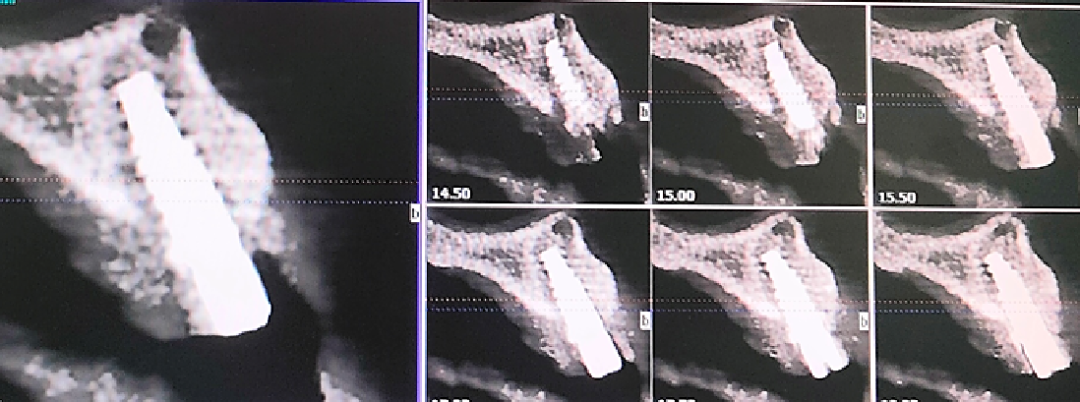

术前CBCT

21颊侧牙槽骨吸收至根尖,腭侧牙槽骨吸收至根尖1/3,根周可见低密度影。牙槽嵴宽度6.41mm。

22冠状位CBCT情况

唇舌牙槽嵴宽度6.41mm,垂直骨缺失1/2,软组织无垂直向缺失。

术后即刻CBCT

术后CBCT

术前术后CBCT对比

唇侧过量植骨希望最终能够实现存量骨组织>2mm。

术后4.5个月CBCT

术后即刻与术后4.5个月CBCT对比

可见种植体唇侧顶端有一定骨粉吸收,但仍在预期范围内。